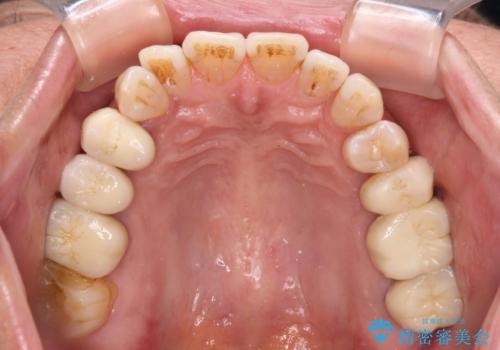

- 治療をおこなって以来、クラウン周りの歯肉から出血が続くとのことで来院された患者様です。

診察を行ったところ、クラウンと歯の境目が不適合で汚れが溜まりやすく、炎症を起こしている状態でした。

他にも、咬合時に痛みを感じる歯や、欠損により咬みにくい奥歯などをインプラントを用いて治療を行うこととしました。